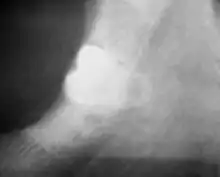

Long-term complications can include periodontal complications such as bone loss on the second molar following wisdom teeth removal. Bone loss as a complication after wisdom teeth removal is uncommon in the young but present in 43% of those of 25 years of age or older.[21] Injury to the inferior alveolar nerve resulting in numbness or partial numbness of the lower lip and chin has reported rates that vary widely from 0.04% to 5%.[21] The largest study is from a survey of 535 oral and maxillofacial surgeons in California, where a rate of 1:2,500 was reported.[25]

Coronectomy

Coronectomy is a procedure where the crown of the impacted wisdom tooth is removed, but the roots are intentionally left in place. It is indicated when there is no disease of the dental pulp or infection around the crown of the tooth, and there is a high risk of inferior alveolar nerve injury.[31]

Coronectomy, while lessening the immediate risk to the inferior alveolar nerve function has its own complication rates and can result in repeated surgeries. Between 2.3% and 38.3% of roots loosen during the procedure and need to be removed and up to 4.9% of cases require reoperation due to persistent pain, root exposure or persistent infection. The roots have also been reported to migrate in 13.2% to 85.9% of cases.[31]